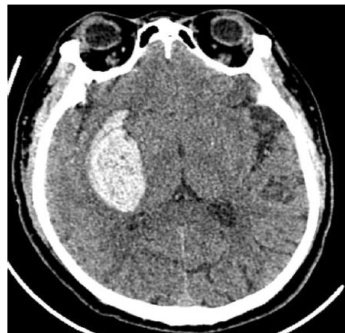

《大医生》杂志(半月刊)是经国家新闻出版广电总局批准,由中国机械工业联合会主管、北京卓众出版有限公司主办的国家级综合性医学学术期刊。本刊以习近平新时代中国特色社会主义思想为指导,紧密跟随世界医学科技发展的潮流,为推动中国医学科技进步和知识创新、促进基层医生医学学术交流和医学事业发展服务,提高基层医疗水平,繁荣中国医学科技出版事业为办刊宗旨。主要栏目有专家特稿、论著、临床研究、中医中药、药物与临床、预防医学、医学影像、病例报告、综述等。是中国医师协会系列期刊,被万方、维普、超星等数据库全文收录。